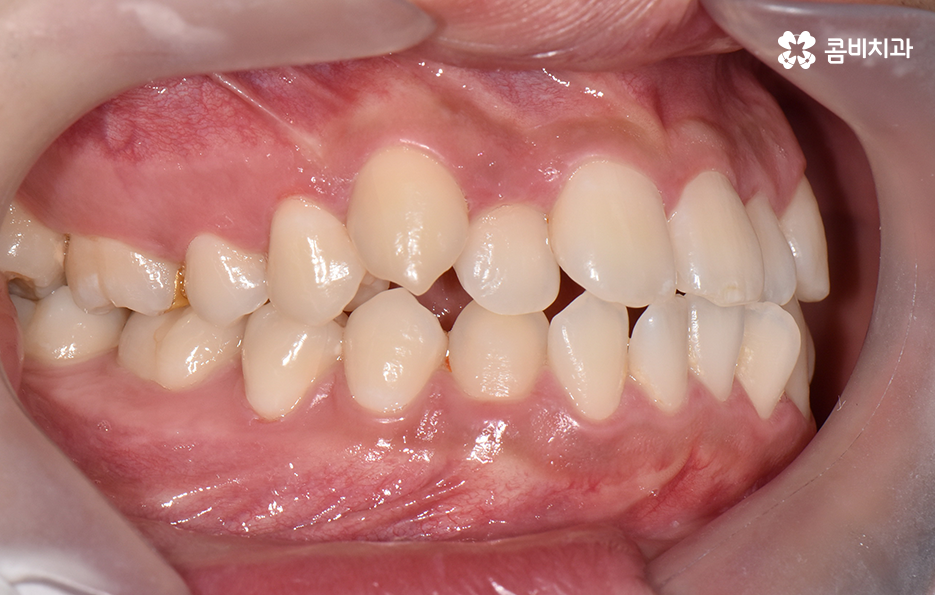

오늘 포스팅에서 보여지는 사진에서는 비발치 교정으로 덧니 교정이 가능했던 사례입니다. 덧니 교정 사례에서 발치교정 케이스는 흔한 치료 방법이긴 하지만 발치에 대한 판단은 치열만이 아니라 골격과 얼굴형을 종합적으로 고려하여 판단하고 치아를 얼마나 이동시켜야 할지 예측하여 판단하기 때문에 3D CT 등의 첨단 장비를 통한 검진과 경험 많은 교정 전문의와 충분히 상의하고 결정해야 합니다

치아교정은 치열을 가지런하게 재배열하는 치료이면서 각 개인의 얼굴형과 골격, 입술라인 등을 종합적으로 고려해야 하기 때문에 발치교정의 필요 여부를 판단하는 것에도 신중한 판단이 필요한데요

30대 치아교정 되도록 빨리 치료가 끝나길 원하시는 분들이 많겠지만 교정 치료는 결과가 중요한 치료이기 때문에 자신에게 적합한 치료 계획을 정교하게 세우는 것이 중요하며 발치는 한번 하면 되돌릴 수 없고 반대로 비발치 교정을 한다고 해도 치료상의 편의성만을 따지는 것이 아니라 결과가 중요하기 때문에 각 환자분들의 얼굴에 잘 어울리는 결과를 얻기 위해서는 비발치 교정이 얼마나 적합한지를 잘 따져봐야 하겠습니다

종합하면 발치교정의 필요성은 얼굴과의 조화, 골격 그리고 교합 등을 전체적으로 고려하여 판단하기 때문에 각 환자분들이 필요한 치아의 이동 정도를 정확히 예측하고 필요한 치아 이동 공간을 확보함에 있어서 발치교정이 적합할지 아니면 비발치적인 방법으로도 치아 이동 공간이 확보 가능한지 따져보고 있으며 발치교정이 아니더라도 치간삭제, 악궁확장, 어금니 후방이동과 같은 방법으로 공간 확보가 가능하기 때문에 각 환자분들에게 적합한 1:1 맞춤형 치료가 진행되고 있어요